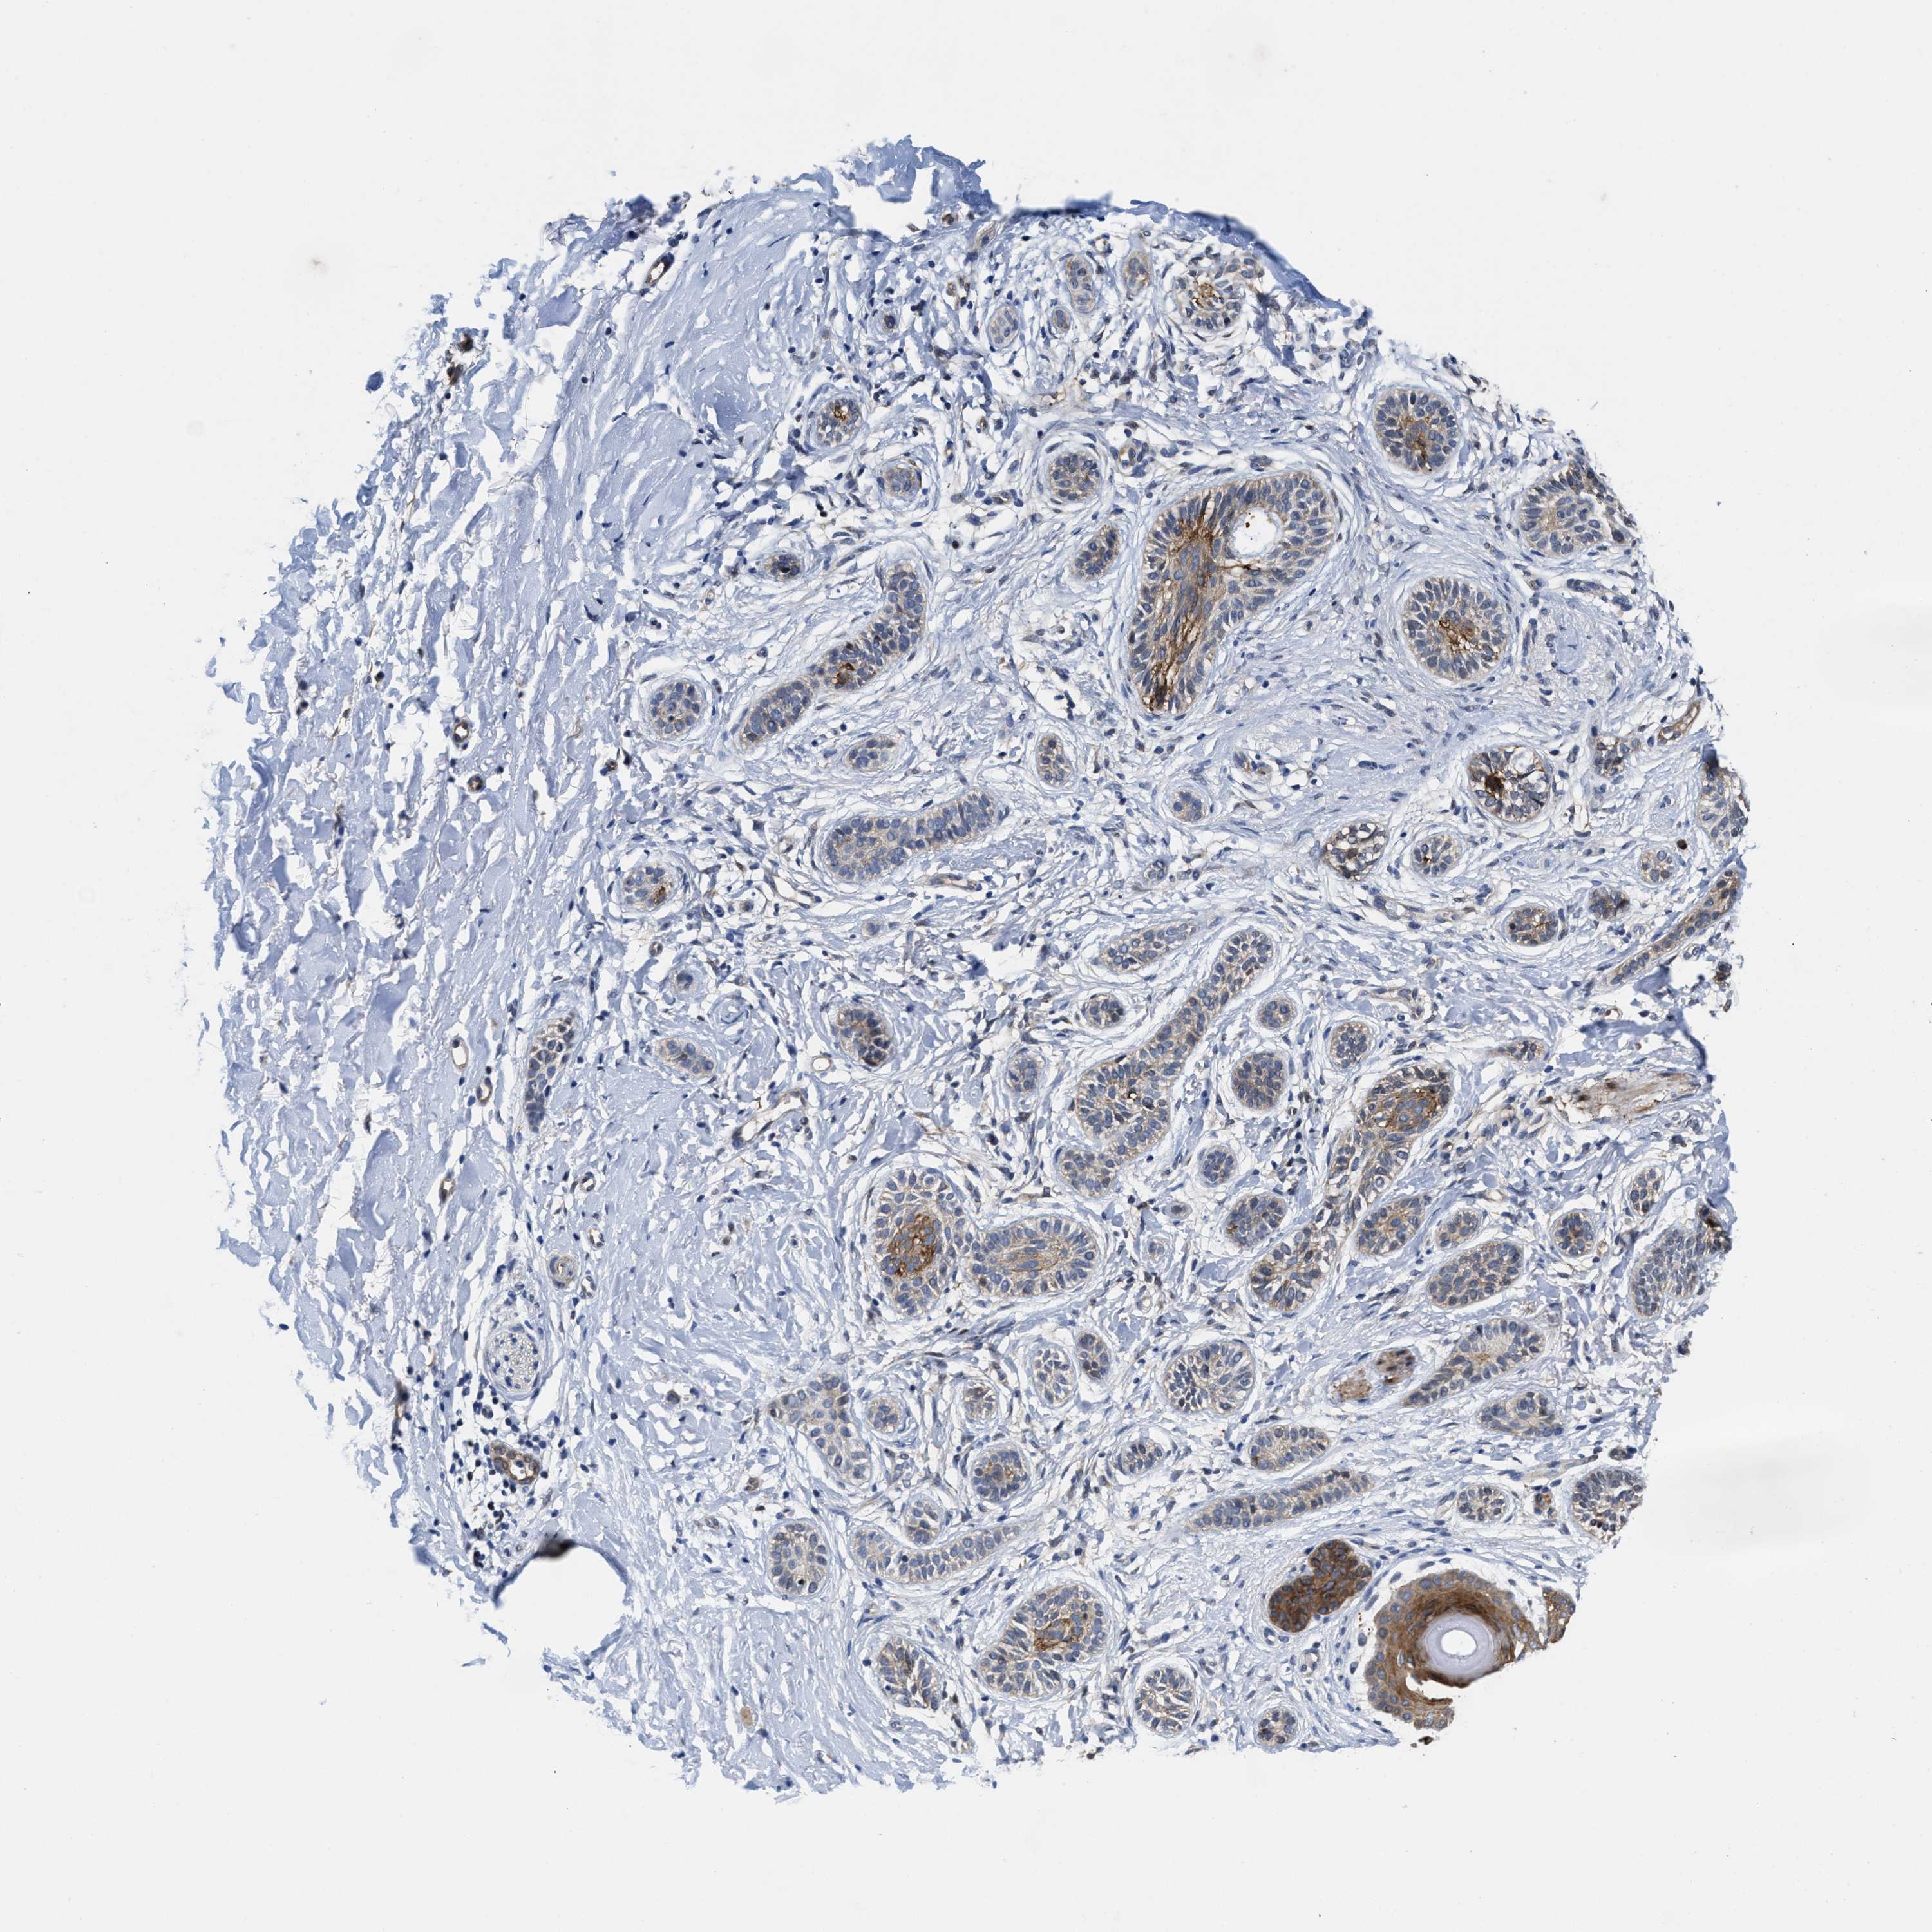

Basal cell and squamous cell cancer

SKIN CANCER - Protein expressioni

A mouse-over function shows sample information and annotation data. Click on an image to view it in a full screen mode. Samples can be filtered based on level of antibody staining by selecting one or several of the following categories: high, medium, low and not detected. The assay and annotation is described here.

Each image is clickable and will lead to virtual microscopy that enables deeper exploration of all samples and also displays staining intensity scores, fraction scores and subcellular localization as well as patient and tissue information for each sample.

Antibody HPA020192

Squamous cell carcinoma, NOS